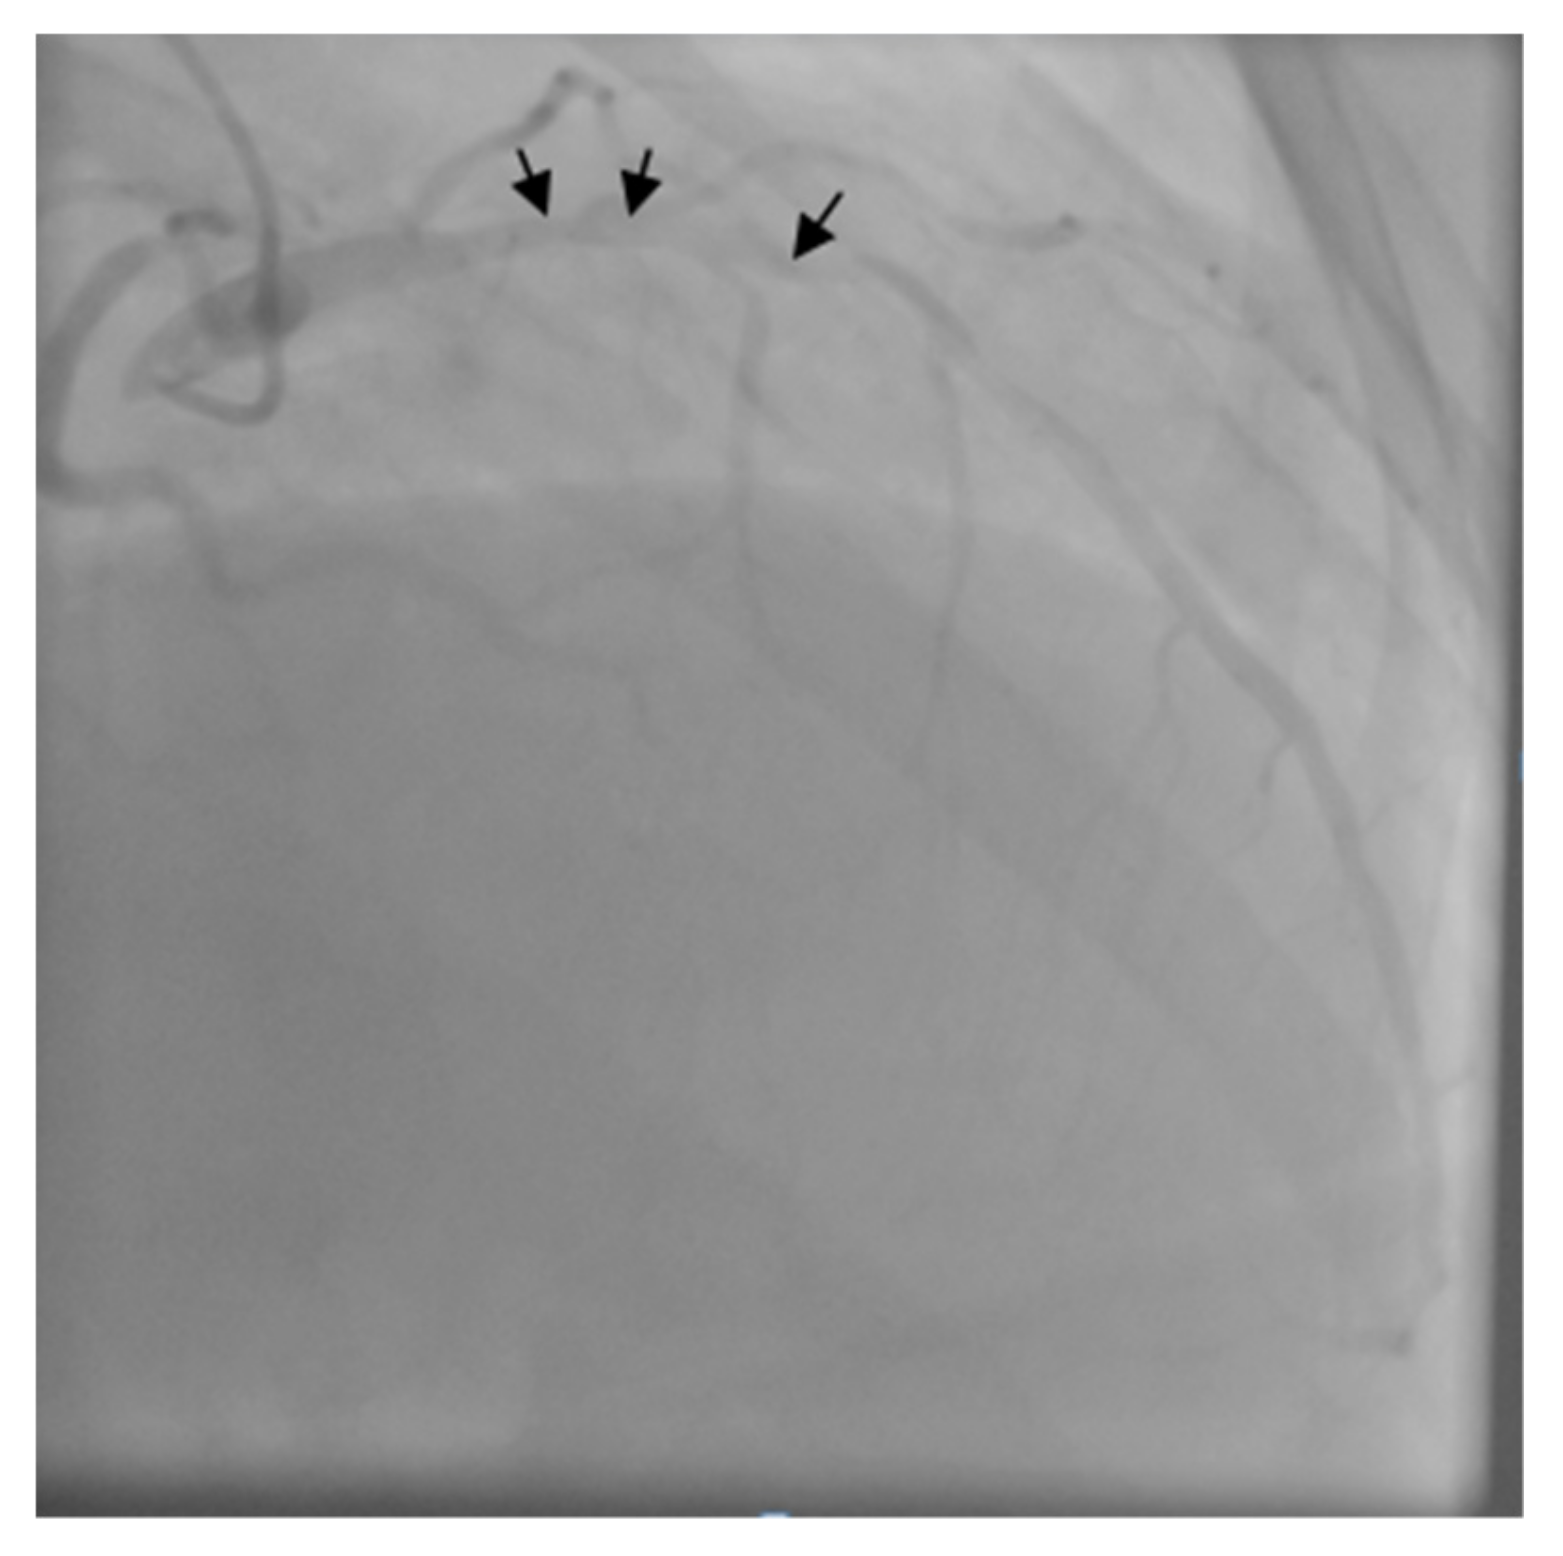

The patient was transferred to the Intensive Care Unit where he received inotropic support with Dobutamine, Levosimendan, and loop diuretics. The coronary angiogram showed a proximal critical stenosis of the left anterior descending artery (LAD) (Figure 5) and a tight lesion of the obtuse marginal (OM1) (Figure 6).

Figure 5. Left coronary angiogram - arrows show severe proximal left anterior descending artery (LAD) stenosis.